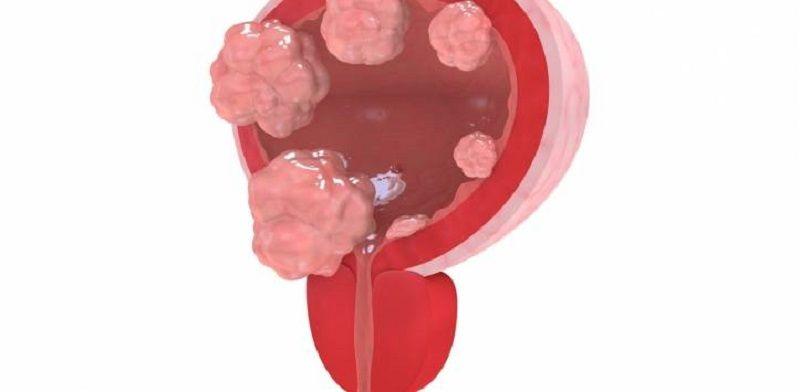

ANMAT aprobó fármaco que mejora la sobrevida en pacientes con cáncer de vejiga avanzado

Erdafitinib es el primer tratamiento oral desarrollado en el mundo para tratar pacientes con metástasis de este tumor, que en el país genera unos 3.700 casos anuales. Según el estudio presentado ante la agencia...